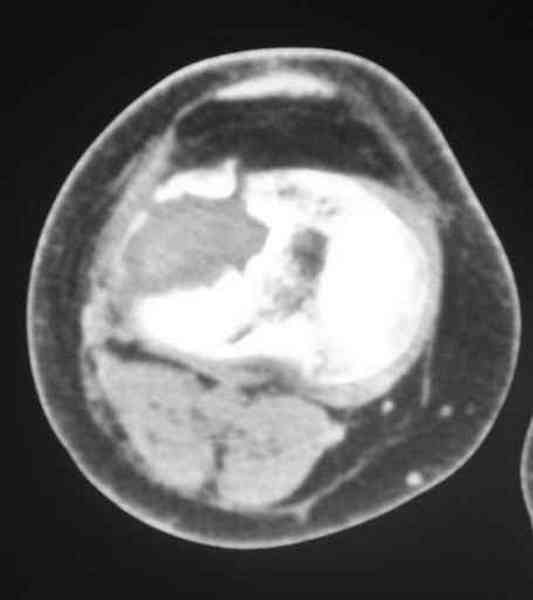

По тактике лечения, более импонирует второй вариант, но наружная плато расколота и туда при нагрузке внедряется н/мышелка бедра, поэтому после дистракции как репонирвать: или стяжными винтами, или изогнутами спицами или субхондральная костная пластика?

Уважаемый Абдурашид. Если нет противопоказаний , то из оперативных способов, я бы рекомендовал следующие: Полное замещение наружного мыщелка аллотрансплантатом либо открытая репозиция с элевацией и замещение дефекта ауто или аллокостью. В Ваших условиях , я бы рекомендовал второй способ. Во-время элевации необходимо разъединить фрагменты со стороны сустава ( надсечь скальпелем по линиям перелома, а затем тонким остеотомом их разъединить. При помощи долота произвести неполную остеотомию ( захватите не менее 1,5 - 2 см губчатой кости и поднять фрагменты, визуально отрепонировать и фиксировать 2-3 спицами. Дефект заместить костным ауто или аллатрансплантатом. Окончательная стабилизация пластиной ( лучше с угловой стабильностью, либо АВФ - позволит спокойно устранить угловую деформацию.